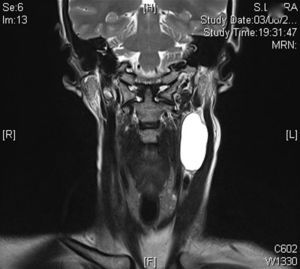

Tras dos años de revisiones clínicas y radiológicas (TC y RNM) según protocolo, aparece, en una RNM de control, una lesión quística, tabicada laterocervical izquierda de aproximadamente 30×20×50mm, que la paciente ya se había notado un mes antes (figs. 1 y 2). A la exploración se aprecia la tumoración claramente en el borde anterior del músculo ECM izquierdo, siendo esta indolora, de consistencia blanda y ligeramente móvil. La paciente se encuentra totalmente asintomática.